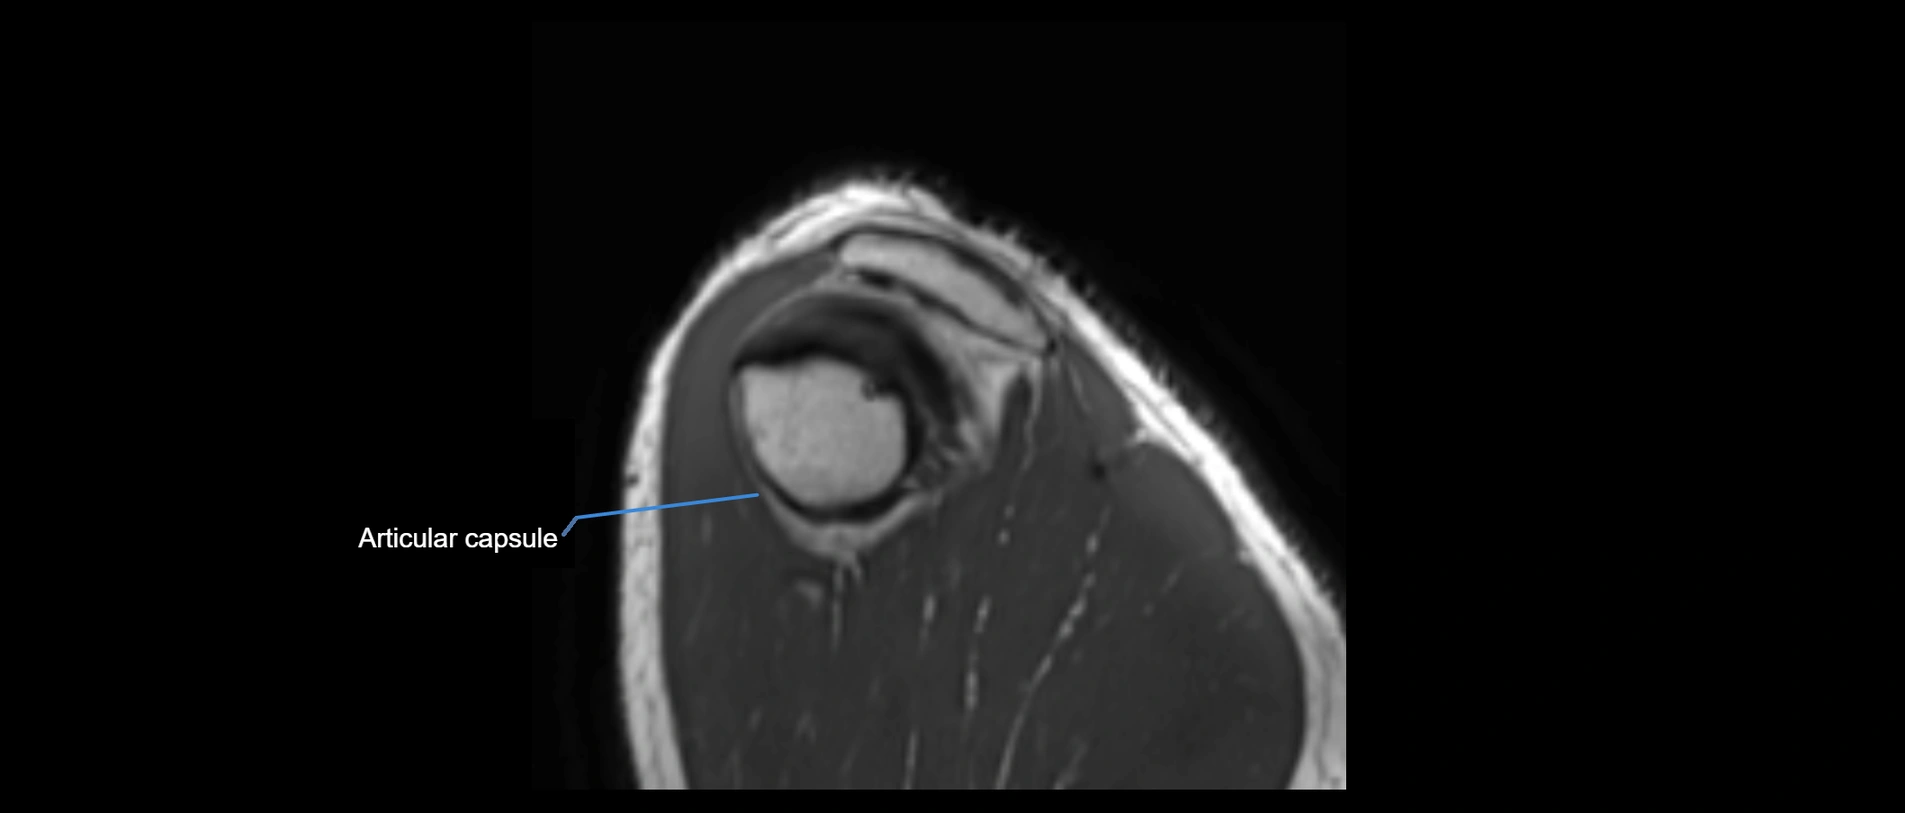

MRI images

image